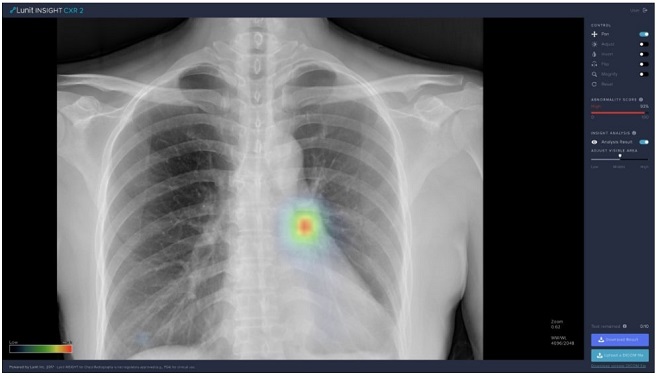

해당 연구를 비롯해 본 사업에서 사용되는 루닛의 폐 질환 진단 보조 인공지능 소프트웨어인 ‘루닛 인사이트 CXR’은 국내 식약처 및 유럽 CE 인증을 받아 국내외 대형 및 종합병원을 비롯한 150여 곳 이상의 헬스케어 기관에서 사용되고 있다.

▲루닛의 폐 질환 진단 보조 AI 소프트웨어인 ‘루닛 인사이트 CXR’로, 인공지능을 활용해 흉부 엑스레이의 비정상 소견을 표시한다.